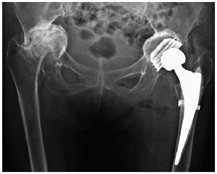

入院后第3天,在腰麻下行左侧全髋关节置换术。患者侧卧位,经改良Hardinge入路逐层切开皮肤、皮下组织及阔筋膜,紧贴臀中肌大转子处附着点,部分切断臀中肌、臀小肌,经股直肌与臀中肌、臀小肌间隙显露关节囊。切除关节囊并处理周围软组织,显露骨折线。用取头器取股骨头,未能顺利取出。经检查见髋臼周缘增生明显致髋臼口狭窄,髋臼口呈握拳状包绕股骨头。换用小号髋臼锉缓慢对股骨头进行磨除,剩余约1/3股骨头时成功将其取出。探查髋臼形态,见髋臼呈"葫芦状"(口小腔大),且髋臼马蹄窝被增生的骨质填充。使用电刀清除软组织,用咬骨钳清除增生骨质,找到真正的髋臼底皮质骨,打磨髋臼。当磨锉至49号时,髋臼锉边缘与髋臼周缘恰好贴合。但由于髋臼腔大口小,髋臼锉未达髋臼底部,无法使用生物性臼杯通过压配的原理进行固定。于外展45°、前倾15°位拧入49号BICON-PLUS螺旋臼(施乐辉,瑞士),检查臼杯稳定性并关窗,置入32号聚乙烯内衬。屈髋并内收、外旋股骨,暴露股骨近端,继续处理股骨侧。使用股骨柄锉扩髓至3号时,股骨矩处骨质出现劈裂,采用捆绑带固定。放置3号股骨柄试模,锥度位于髋臼上缘约5 cm处,复位困难。改用0号股骨柄假体(Polarstem,施乐辉,瑞士),打入骨水泥固定。骨水泥凝固后安装32+0号黑晶球头(施乐辉,瑞士),复位髋关节。检查关节活动度,屈髋、内收、外展、外旋均无脱位。术后摄髋关节正位X线片,观察假体位置(图3)。